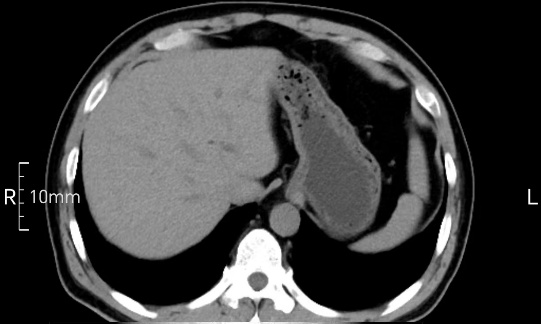

看看下面三幅便知遵醫(yī)囑的重要性。

沒禁食,胃內(nèi)全是食物,導致胃壁顯示不清。

禁食但檢查前沒有喝飽,胃未能漲開,胃壁觀察效果不佳。

完美禁食且喝飽飽,胃壁完美展現(xiàn)。

CT檢查前的“禁食”和“喝飽”,看似矛盾,實則合情合理,分工合作:空腹:是為了讓上腹部(肝膽胰脾腎等)的圖像清晰無干擾,并保障檢查安全。喝水:有效的充盈胃部和、腸道使圖像清晰呈現(xiàn)。兩者巧妙配合,都是為了給您一個最精準的診斷結果。